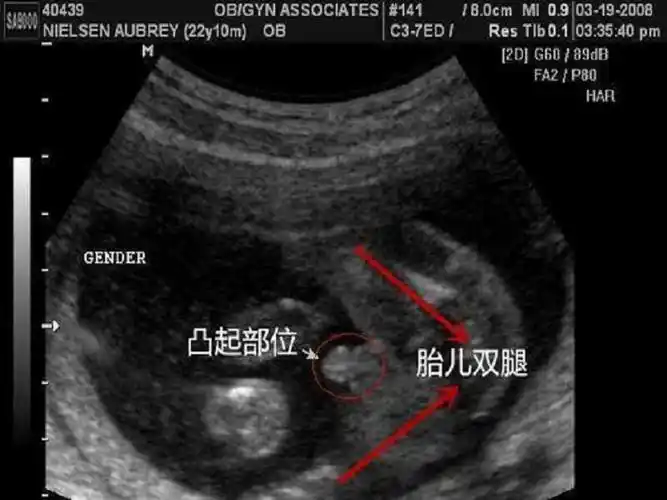

nt怎么看男女宝宝最准 抓住这2处一秒分辨

12周胎儿男女生殖图区别图

2:b超的准确性有误差胎儿在4个月的时候就可以检测到性别了,其中男